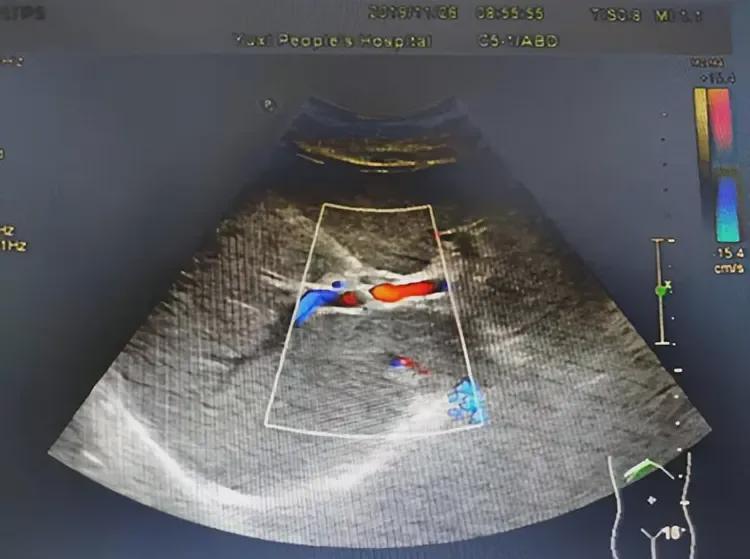

为了验证自己的猜想,叶阿姨前往医院进行了彩超检查。检查结果显示,她的左附件区有一个小囊肿,约2.7×2.4CM,伴有囊性回声,盆腔还有少量积液。然而,叶阿姨却将囊性回声误认为是监听器。

法官在审理此案时,也觉得十分奇葩。为了查明真相,法官将叶阿姨送到另一间医院进行检查。检查结果显示,她的子宫内并没有“监听器”等异物,只有囊性回声存在。然而,叶阿姨却仍然坚持认为囊性回声就是“监听器”。法官在啼笑皆非之余,驳回了叶阿姨的赔偿诉求。

其实,从普通的科学常识就可以判断,医生在子宫内安装监听器是无稽之谈。子宫内环境潮湿、缺氧且含有腐蚀性体液,电子设备无法在其中长期工作。此外,医用植入设备需要体外充电或定期更换,无法隐匿近十年之久。而且,彩超对金属异物敏感度高,若有监听器必然会被发现。

因此,叶阿姨所述的“监听器”实为卵巢囊肿(囊性回声),这是一种常见的良性病变,可能引发腹痛。叶阿姨用手机播放歌曲时偶尔与腹痛巧合,于是形成了“被监听”的幻想,这实际上属于被害妄想症或躯体化障碍。